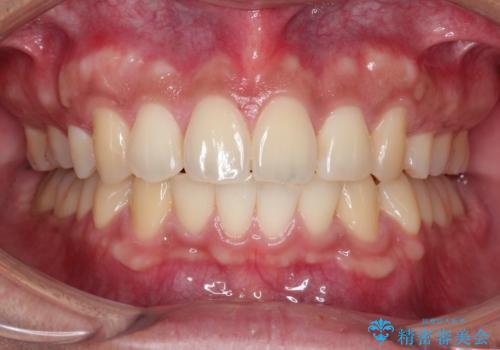

- 凸凹を治したいと来院された患者様です。

インビザラインにて、遠心移動を行いながら綺麗に配列することができました。